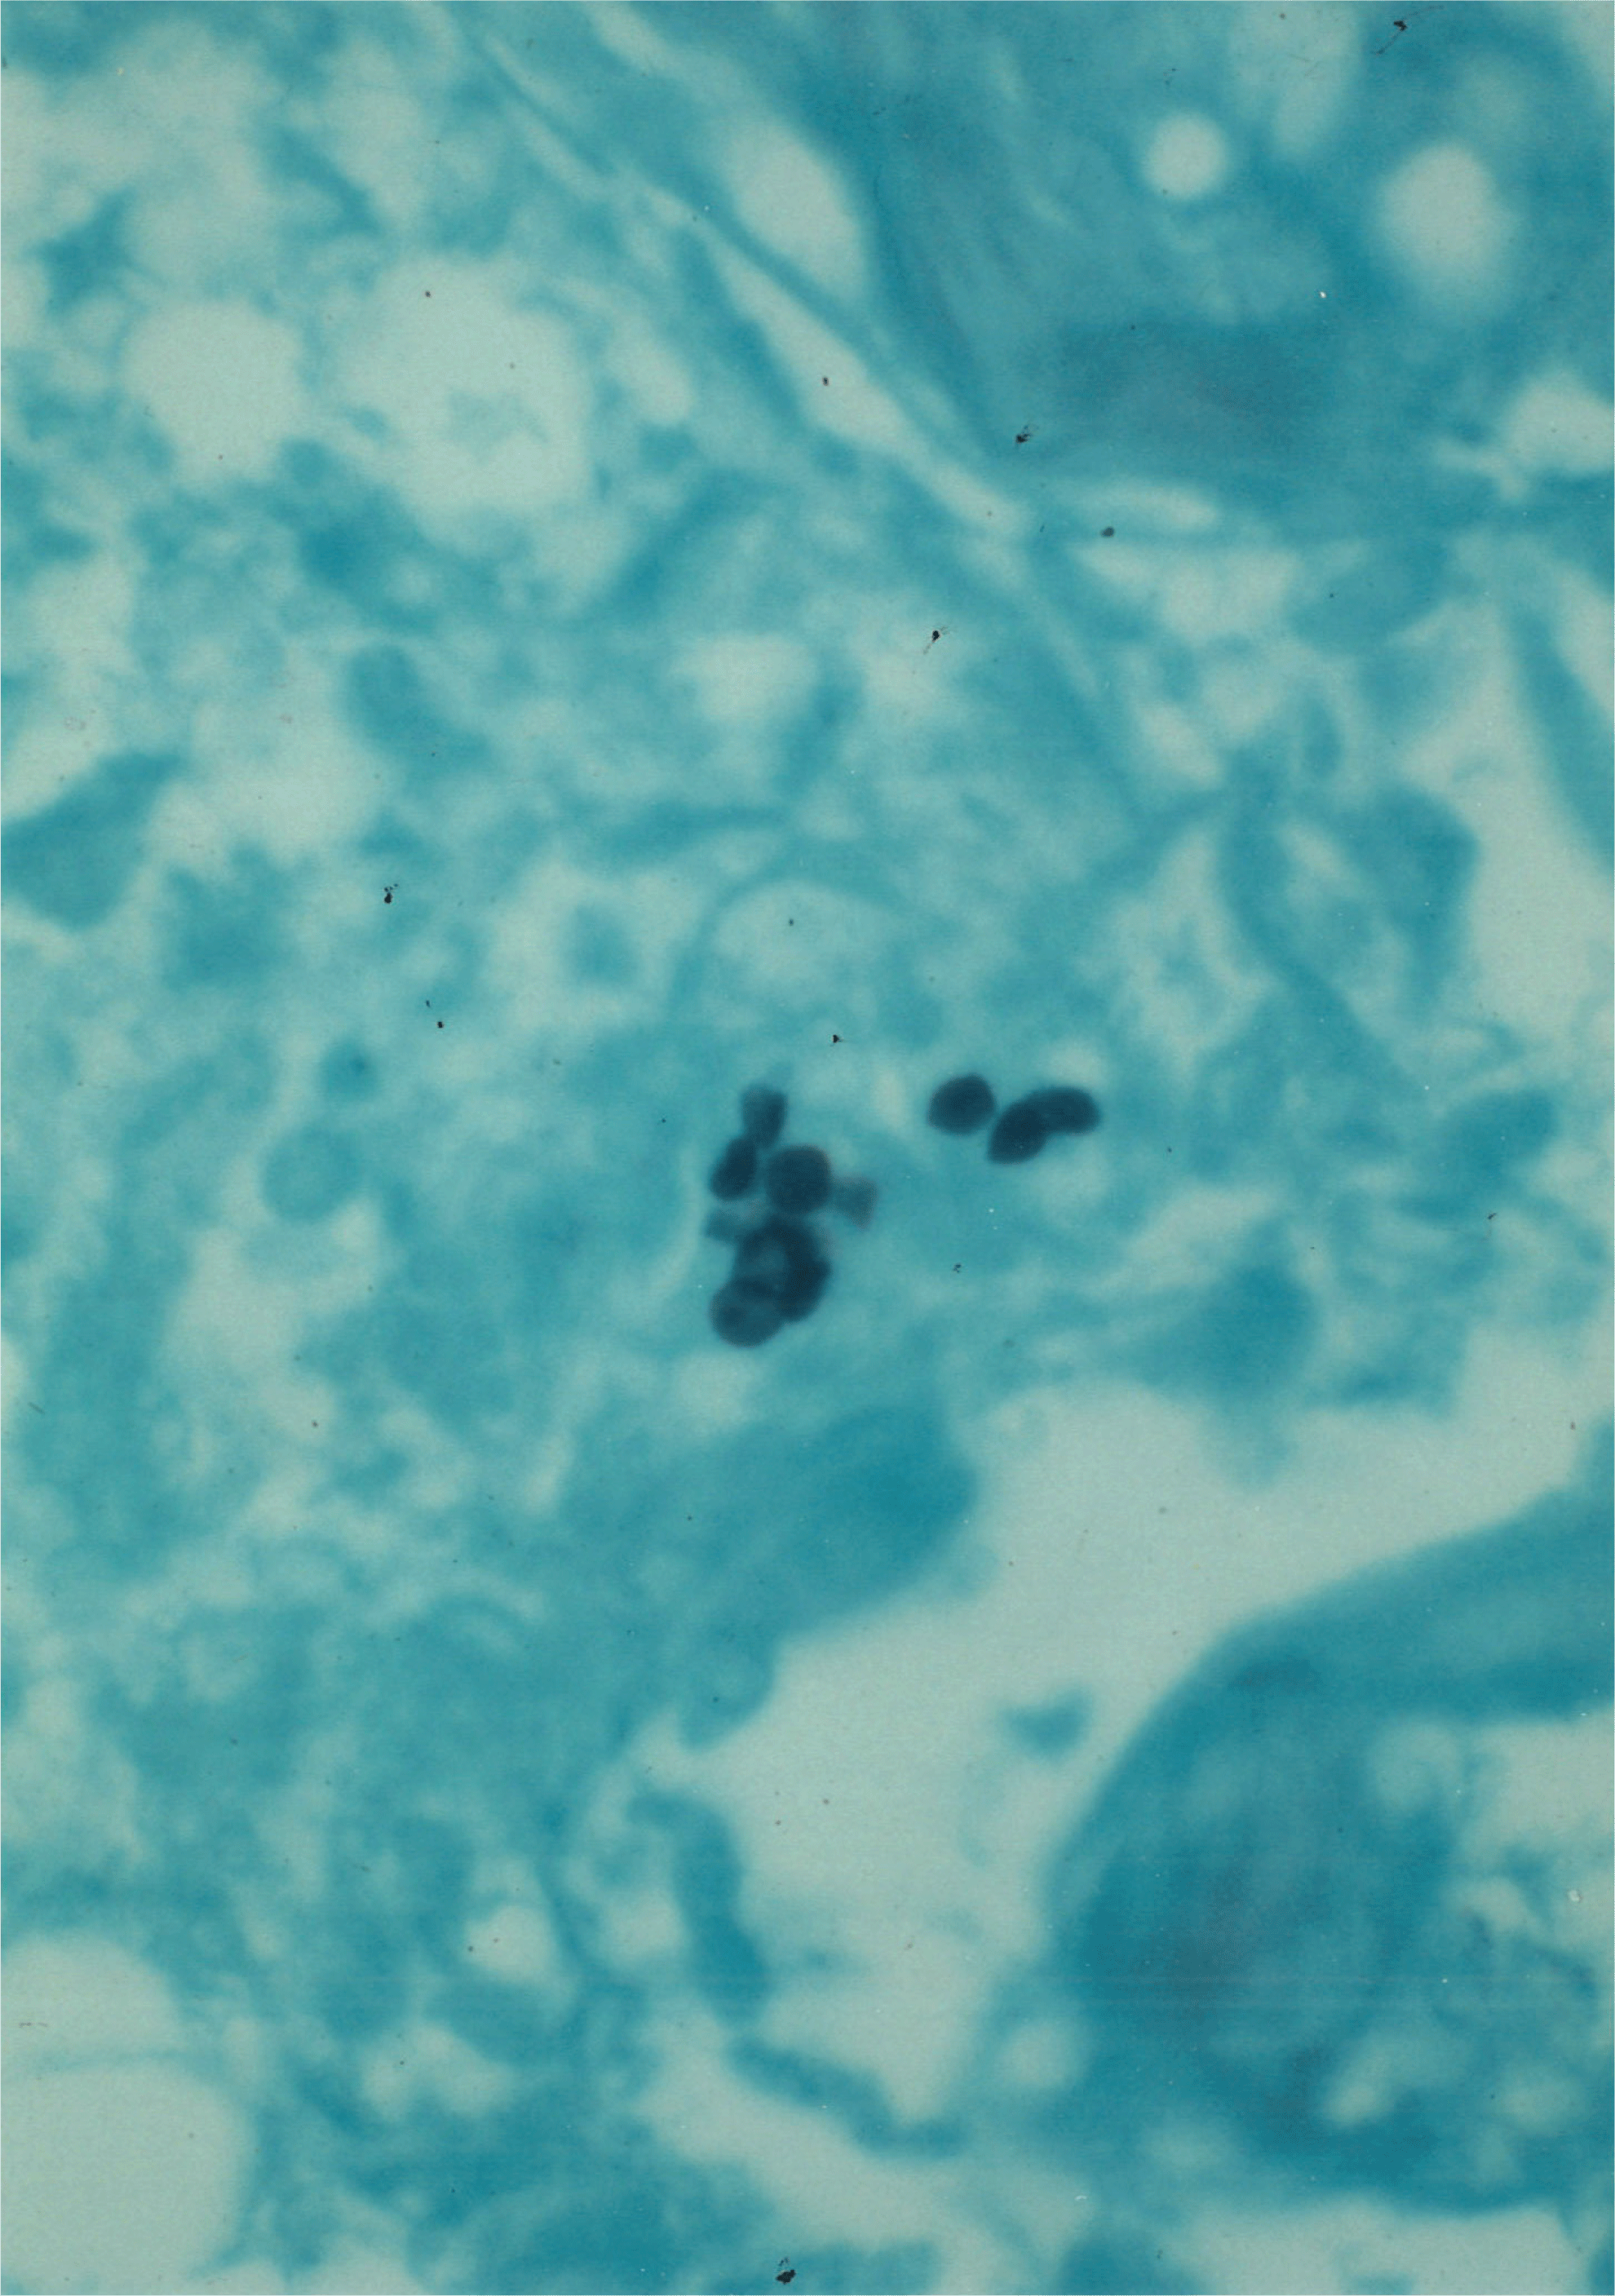

Parenchymal Kidney Disease: Paraproteinemia and Deposition Diseases

- Enhanced understanding of ALECT2 amyloidosis

- Best practice for typing of amyloidosis

- Evidence for distinguising among diseases with organized deposits